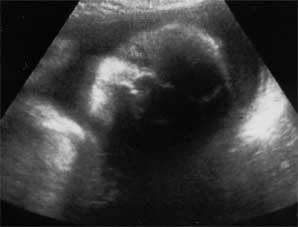

Now for the fun part... Pictures!!

The picture on the left is of her face, straight on. The left side of her face is in shadow, but you can clearly see her right eye, her nose, and her lips. Isn't that amazing?! Our little Ella has a face! I can't wait until the 4-D ultrasound. One good thing about having plenty of amniotic fluid is that the ultrasound pictures come out really good.